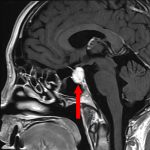

658

'25年7月

70代

脳幹腫瘍

頭蓋内腫瘍摘出術

No.’25_60 手術前1

No.’25_60 手術前2

No.’25_60 摘出 前

No.’25_60  摘出 中

No.’25_60 摘出 後